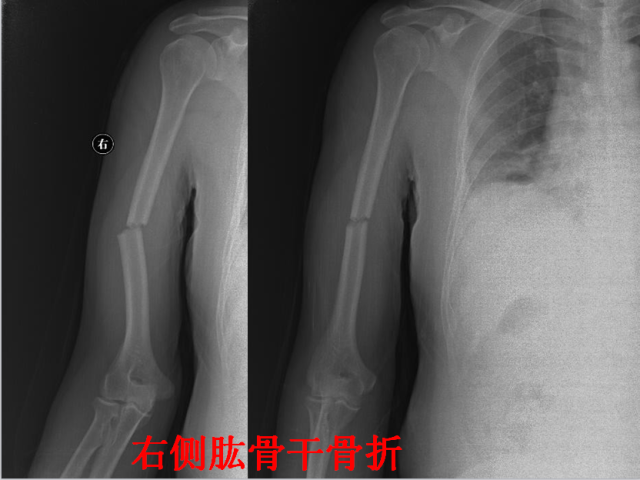

骨折篇

01

定义:骨折{Fracture}是指骨的完整性和连续性的折裂或粉碎。包括创伤性骨折、疲劳性骨折和病例理性骨折。 临床上以创伤性骨折*常见。